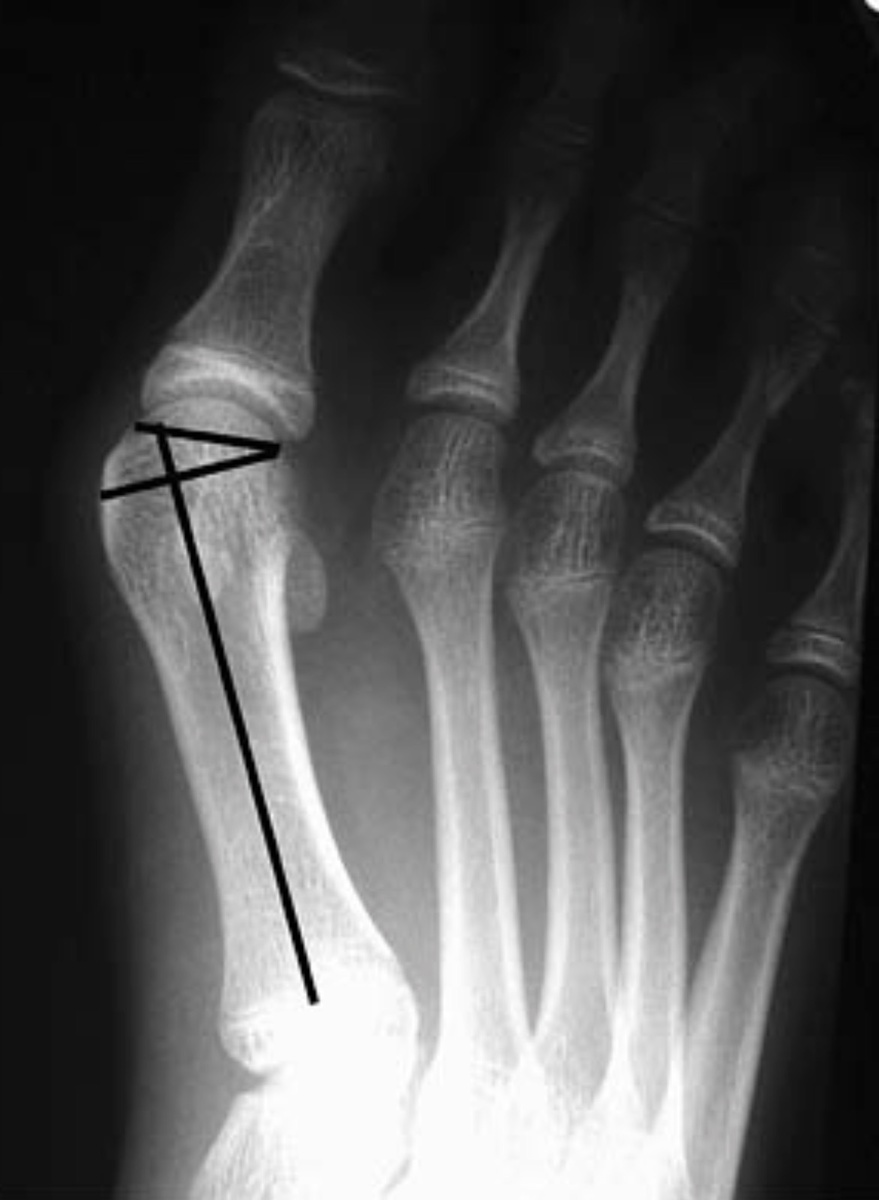

Ортопед объяснил, почему появляется шишка на большом пальце ноги

Врач высшей категории, травматолог-ортопед «СМ-Клиники», кандидат медицинских наук Михаил Дорошев рассказал, что влияет на развитие вальгусной деформации стопы (шишки на большом пальце ноги) и что может помочь. Врач отметил, что по его собственному опыту «та самая шишка на первом пальце стопы не появляется и не проходит сама по себе». Причин у подобной деформации может быть много. Среди основных факторов регулярное ношение неудобной и неподходящей обуви (в этом случае нарушается амортизация стопы), «нагрузка на стопу распределяется неравномерно, и в итоге страдают все отделы стопы, в том числе и плюсневые кости». Но повлиять на появление вальгусной деформации стопы могут травмы, особенно у спортсменов. Это может привести к разрывам сухожилий и травмам костей. Этот фактор — предпосылка к образованию шишки в месте перелома плюсневой кости. Повлиять могут и болезни, среди которых генетические, ревматоидный артрит, артроз, поражающие в том числе суставы стопы. Эти заболевания провоцируют д

Врач высшей категории, травматолог-ортопед «СМ-Клиники», кандидат медицинских наук Михаил Дорошев рассказал, что влияет на развитие вальгусной деформации стопы (шишки на большом пальце ноги) и что может помочь.

Врач отметил, что по его собственному опыту «та самая шишка на первом пальце стопы не появляется и не проходит сама по себе». Причин у подобной деформации может быть много.

Среди основных факторов регулярное ношение неудобной и неподходящей обуви (в этом случае нарушается амортизация стопы), «нагрузка на стопу распределяется неравномерно, и в итоге страдают все отделы стопы, в том числе и плюсневые кости».

Но повлиять на появление вальгусной деформации стопы могут травмы, особенно у спортсменов. Это может привести к разрывам сухожилий и травмам костей. Этот фактор — предпосылка к образованию шишки в месте перелома плюсневой кости.

Повлиять могут и болезни, среди которых генетические, ревматоидный артрит, артроз, поражающие в том числе суставы стопы. Эти заболевания провоцируют дегенерацию плюсневых костей, что связано с развитием шишки на ноге.

К дополнительным причинам могут относиться лишний вес, постоянная работа на ногах, плоскостопие.

А способ избавиться от шишки на ноге один — операция. Только так можно выздороветь и избавиться от боли.

«Если вы думаете, что про шишку на ноге можно просто забыть, достаточно поносить некоторое время ортопедические стельки, то глубоко заблуждаетесь. Последствия вальгусной деформации могут быть крайне неприятными. Прежде всего, это резкая боль при ходьбе и, как результат, стеснение движений. Согласитесь, никто в такой ситуации не готов это постоянно терпеть. Поэтому я как врач вижу единственный выход — в хирургическом удалении шишки», — подчеркнул специалист.